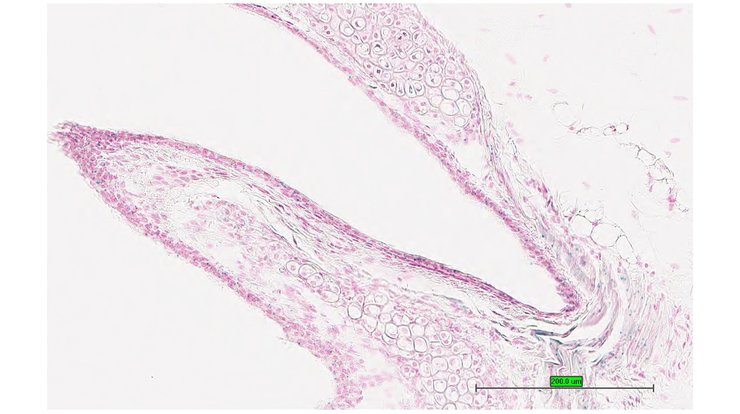

TS28: eye Present UC Davis_1866059